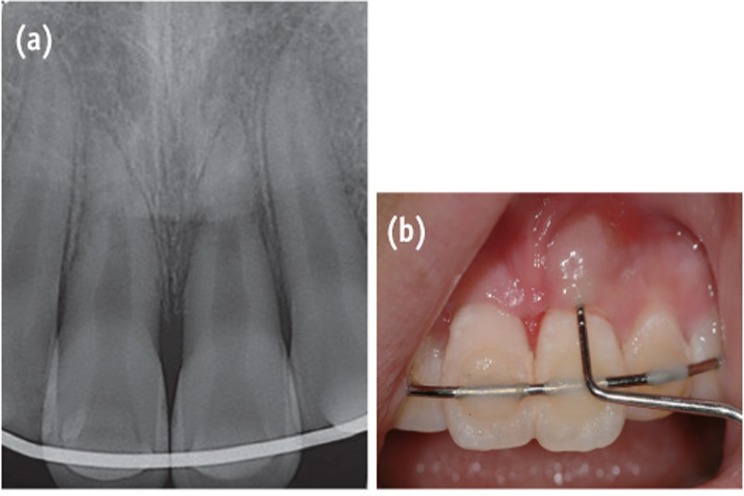

One week after the trauma, both teeth had a normal response to pulp vitality tests. Three weeks later, localized swelling was observed on the labial gingiva of the maxillary left central incisor, and a radiolucent lesion was present near the fracture line. Both teeth had no responses to the thermal and electronic pulp tests. The narrow and deep pocket (approximately 8 mm) were explored by a dental probe through the gingival sulcus to the swollen portion (Figure 5). Root canal treatment was initiated on both coronal fragments of the teeth with K-file and irrigated with 5% sodium hypochlorite. Working length was established with an apex locator (DentaPort ZX). Calcium hydroxide was applied into the canals between appointments. The deep pocket was debrided because of the possibility of the insertion of a foreign body at the time of the accident. At the 2-month follow-up evaluation, the swelling had disappeared and pocket depth was reduced to 3 mm. The canals were obturated with MTA (ProRoot) confined to the coronal fragment (Figure 6a).

Figure 5

Images were obtained 3 weeks after the trauma. (a) The periapical radiograph shows a radiolucent lesion around the fracture line on tooth #21; (b) The clinical photograph shows narrow and deep pocket depth and gingival swelling on tooth #21.